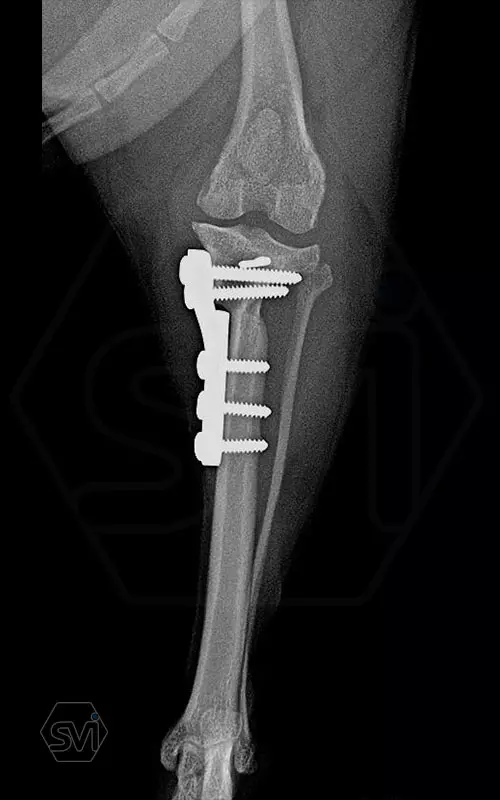

Introducing the TPLO-M „terraced” plate family from Smartvetimplants.com

In small dogs, medial patella luxation (MPL) and the rupture of anterior cruciate ligament (RACL) often occur simultaneously. During the surgical procedure, the joint must be stabilized and the patella fixed in the middle axis at the same time.

The solution of Smatvetimplants is the TPLO-M plate family with terrace:

Small TPLO-M plate:

part of a polyaxial locking system, symmetrical, available with 2.5 and 4.0mm terraces, torx-head, 2.4mm locking screws (2.0 and 2.4mm AO screws can also be inserted), material steel. Optimized for R12 and R15 blades.

Between October 2020 and December 2021, we performed 19 TPLO-M surgeries at the Animal Hospital in Nyíregyháza,: 16 times used the mini (2.0 R12) and 3 times the small (2,4 R15) TPLO-M plate.

The experience is very encouraging, we find the system and plates suitable for the simultaneous treatment of MPL and RACL. ( in case of 4/4 pat. lux. also). We will back soon with details.